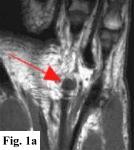

MRI FINDINGS:   MRI was performed on AIC's high-field 1.5 Tesla short-bore Siemens Symphony scanner using a small flexible surface coil. Fig. 1a is a high-resolution coronal DESS, Fig. 1b a sagittal T1 weighted, Fig. 1c a sagittal turbo STIR, and Fig. 1d an axial T1 weighted. They demonstrate a 5x5x7 mm nodule in the volar aspect of the hand at the level of the 4th MCP joint inseparable from the flexor digitorum superficialis tendon (arrows) with some adjacent soft tissue edema. The underlying tendon and bones are otherwise intact.

DIFFERENTIAL DIAGNOSIS:   Based on the MRI findings the DDX includes a benign soft tissue tumor such as a xanthoma, fibroma, hemangioma, neuroma or a lesion related to the tendon sheath such as a giant cell tumor of the tendon sheath or tendinous xanthoma. An inflammatory node was also in the differential. It does not have the MRI characteristics of a cyst or ganglion.

SURGICAL-PATHOLOGIC DIAGNOSIS:   The patient was taken to surgery at LCH by Dr. Rahmati and a "rather solid round mass attached to the volar aspect of the 4th tendon sheath" (arrows in Fig. 2a-b) was excised measuring about 4x4x3 mm. Pathology at LCH revealed a "grayish-white somewhat nodular smooth soft tissue measuring 9x8x5 mm" with histopathologic "features in favor of a giant cell tumor of tendon sheath" interpreted as benign.